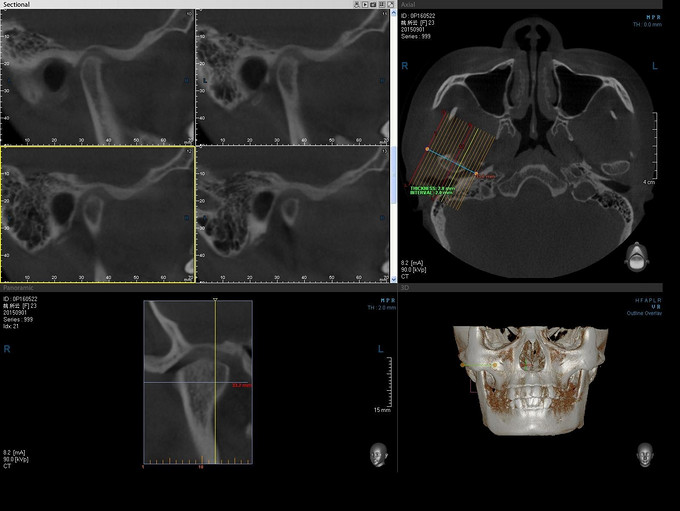

青年女患者,慢性病程,患者一年前始出现右侧颞下颌关节区咬硬物时弹响,无诉疼痛,未予治疗。半年前出现右侧颞下颌关节咬物弹响伴疼痛,三月前出现左侧颞下颌关节区咬物弹响,伴轻微疼痛。今为进一步治疗来我院就诊,门诊以"双侧TMD"收入院

双侧颞下颌关节区轻压痛,张口度约3cm,张口型“>”张闭口时右侧颞下颌关节区可触及绞索感,伴轻度疼痛。侧方咬合:左侧3mm,右侧1mm;前伸牙合无障碍。

诊断:1.双侧颞下颌关节不可复性盘前移位2.右侧颞下颌关节盘穿孔,全麻下行右侧颞下颌关节盘穿孔修补术+关节盘松解复位术+髁突磨削术+关节成形术+邻近瓣转移修复术+左侧颞下颌关节灌洗术+关节盘松解复位术。